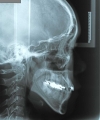

日本矯正歯科学会専門医課題症例(第6症例)

カテゴリー:Class Ⅲ (抜歯症例)

出題基準:大臼歯関係がclass Ⅲで、少なくとも前歯部が反対咬合または切端咬合で、ANB 0度以下が望ましい。条件は第5症例と同じだが、こちらは抜歯して治療して良い。

初診時